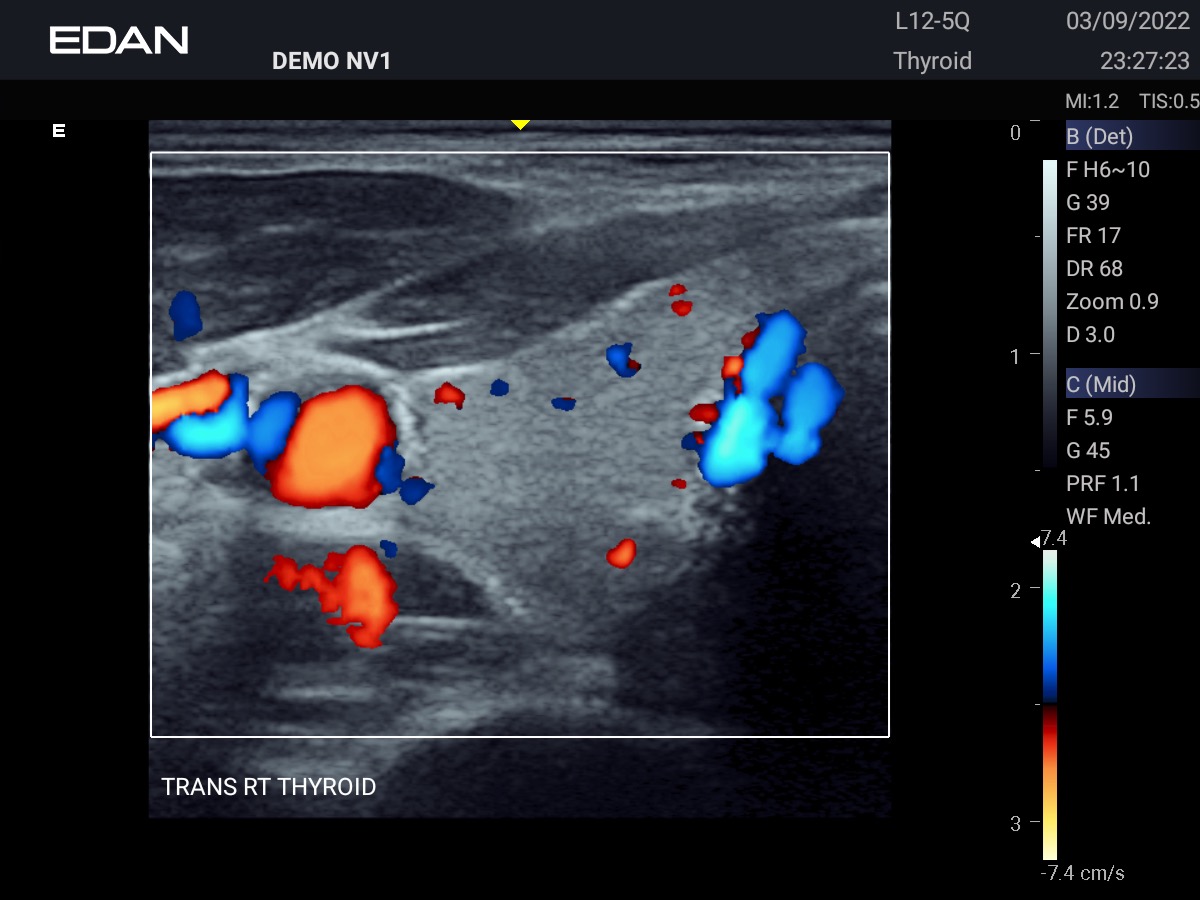

Clareza impressionante

Construído com a inovadora tecnologia Edan TAI e várias tecnologias de processamento de imagem, o Acclarix AX3 pode exibir perfeitamente a imagem de ultrassom em diferentes modos, auxiliando o ultrassonografista a fazer diagnósticos mais precisos.

Galeria de Imagens